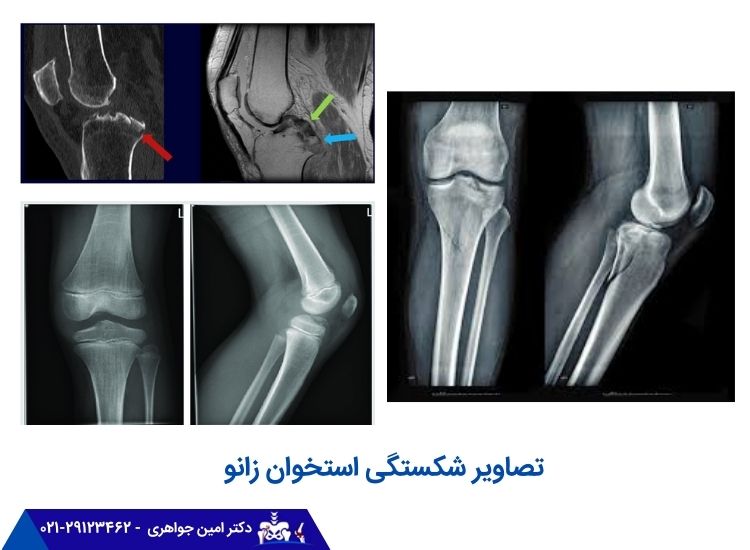

البته از روی چنین نشانهها و علائمی نمیتوان بهدرستی تشخیص داد که آیا علت درد شکستگی است یا چیز دیگری؛ زیرا بیماریها و اختلالات زیادی در زانو هستند که باعث بروز چنین مشکلاتی میشوند. تشخیص دقیق شکستگی به وسیله بررسی تصاویر رادیوگرافی انجام میشود. پزشک پس از بررسی عکس شکستگی زانوی پا، روش درمان را پیشنهاد میدهد.

پزشک از تستهای تصویربرداری برای تأیید شکستگی زانو و ارزیابی میزان آن استفاده میکند. این تستها شامل موارد زیر هستند:

- عکس رادیولوژی (x-ray): عکسهای رادیولوژی تصاویر دقیقی از شکستگی زانوی پا ارائه میدهند و اغلب میتوانند شکستگیهای مختلف، محل آنها و هرگونه جابجایی یا ناهماهنگی استخوانها را نشان دهند.

- تصویربرداری تشدید مغناطیسی (MRI): امآرآی از میدانهای مغناطیسی و امواج رادیویی برای تولید تصاویر دقیق از مفصل زانو، شامل استخوانها، بافتهای نرم و رباطها استفاده میکند. این تصاویر به ارزیابی میزان شکستگی، آسیبهای مرتبط و شناسایی هرگونه آسیب به ساختارهای اطراف کمک میکنند.

- اسکن توموگرافی کامپیوتری (CT): در برخی موارد، ممکن است از سیتی اسکن برای به دست آوردن تصاویر دقیقتر از مفصل زانو استفاده شود. اسکنهای CT میتوانند تصاویر مقطعی ارائه دهند و امکان ارزیابی جامعتر شکستگیهای پیچیده را فراهم کنند.